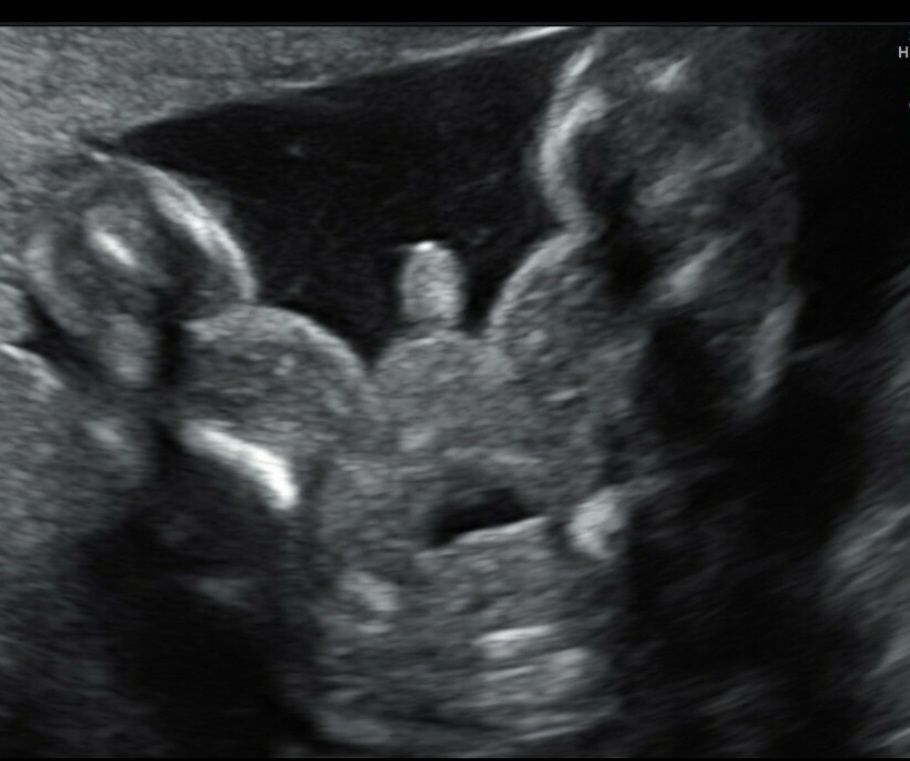

Для сравнения мой мальчик на том же сроке. А у Вас, действительно, похоже на девочку. Изображение

Мне тоже кажется девочка)

На 16 неделе уже точно можно сказать пол, в 12 просто предполагают, я всегда хожу в 16 недель на узи, чтобы пол узнать и всегда говорили точно. У вас скорее всего девочка, у моих мальчишек в 16 недель прям видно было все при любом ракурсе